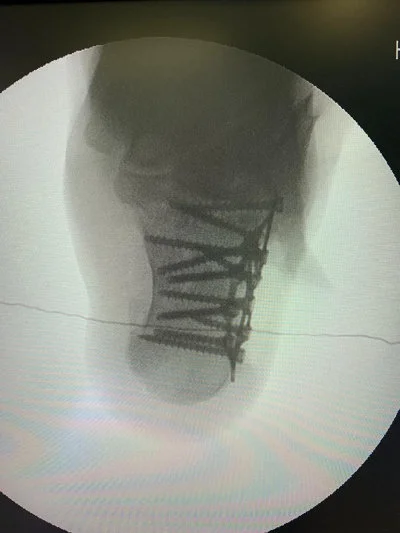

Kas-iskelet sisteminin tüm kırık ve çıkıkları, kas, tendon ve sinir yaralanmaları geniş bir yelpazeyi kapsamaktadır. Her kırık kendi özelinde ayrı ayrı değerlendirilmeli ve her kırık için ameliyat planlaması bu bağlamda yapılmalıdır. Özellikle pelvis-asetabulum kırıkları ortopedik travmada bizler için önemli bir yer tutmaktadır. Bu bölge kırıklarını başarı ile tedavi etmekteyiz.

Özellikle kalça, diz, omurga, kol ve bacak kırıkları gibi durumlarda hızlı ve doğru müdahale, iyileşme sürecini büyük ölçüde etkiler.

Prof. Dr. Halil Burç kliniği olarak, bu tür acil durumlarda sadece yaraları dikmek ya da kırığı sabitlemekle yetinmiyor; hastanın uzun vadeli hareket kabiliyetini, konforunu ve yaşam kalitesini korumayı hedefliyoruz. İleri düzey tekniklerle yapılan ameliyatlar sayesinde, hastalarımızın günlük yaşamlarına en kısa sürede ve en az sakatlıkla dönebilmesi için çalışıyoruz.